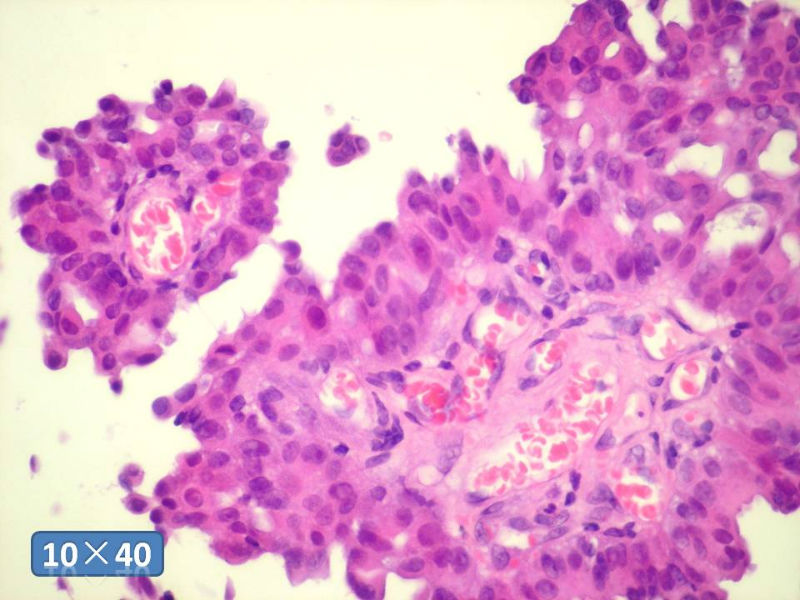

只能说是乳头状瘤

是不是导管内

乳头状瘤 and 导管内乳头状瘤 are the same; Benign lesion.

After you work up and you still cannot be sure it is benign , atypical or maignant lesion, you can call 乳头状lesion.

If this is excisonal case, you should figure out the nature of the papillary lesion.

我的意思就是提醒大家 在不是很确定的情况下 尽量少给自己套枷锁